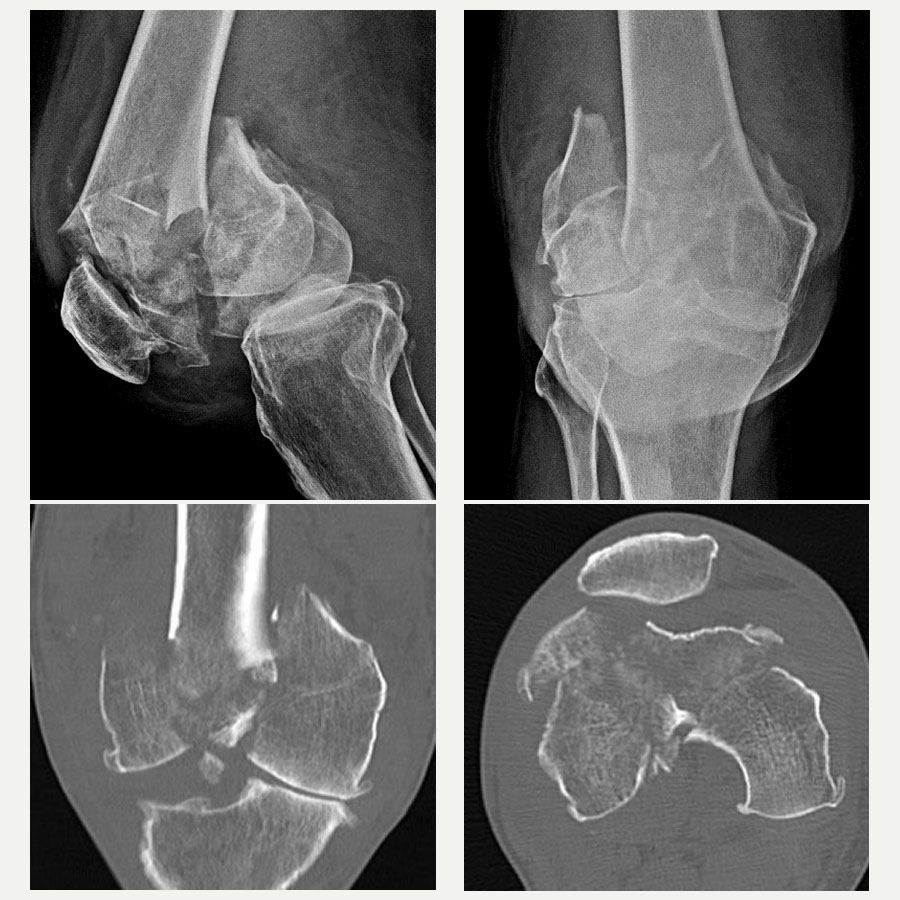

A 58-year-old farmer, the patient had always been physically active despite some age-related degenerative changes in his knees. His injury occurred from a fall in which he landed directly on his knee, resulting in a highly comminuted fracture. On initial inspection, the fracture resembled a shattered stone, with seven to eight individual fragments within the knee joint. These fragments included articular surfaces critical for knee function, making the restoration of joint congruity both urgent and exceptionally challenging.

The complexity of the injury required a structured, multi-step approach, starting with comprehensive imaging. While X-rays provided an initial overview, it was the CT scan that delivered the critical 3D visualization of the fracture pattern. This enabled precise identification of each fragment and helped enormously in preoperative planning.

Such advanced imaging is essential for joint injuries where the accuracy of reduction dictates functional outcome. It allowed me to mentally reconstruct the knee and consider the tools and implants I would need. A detailed plan was then developed with contingencies in place—Plan B, and Plan C etc—including alternatives for fixation devices that might not conform to standard knee fracture patterns.